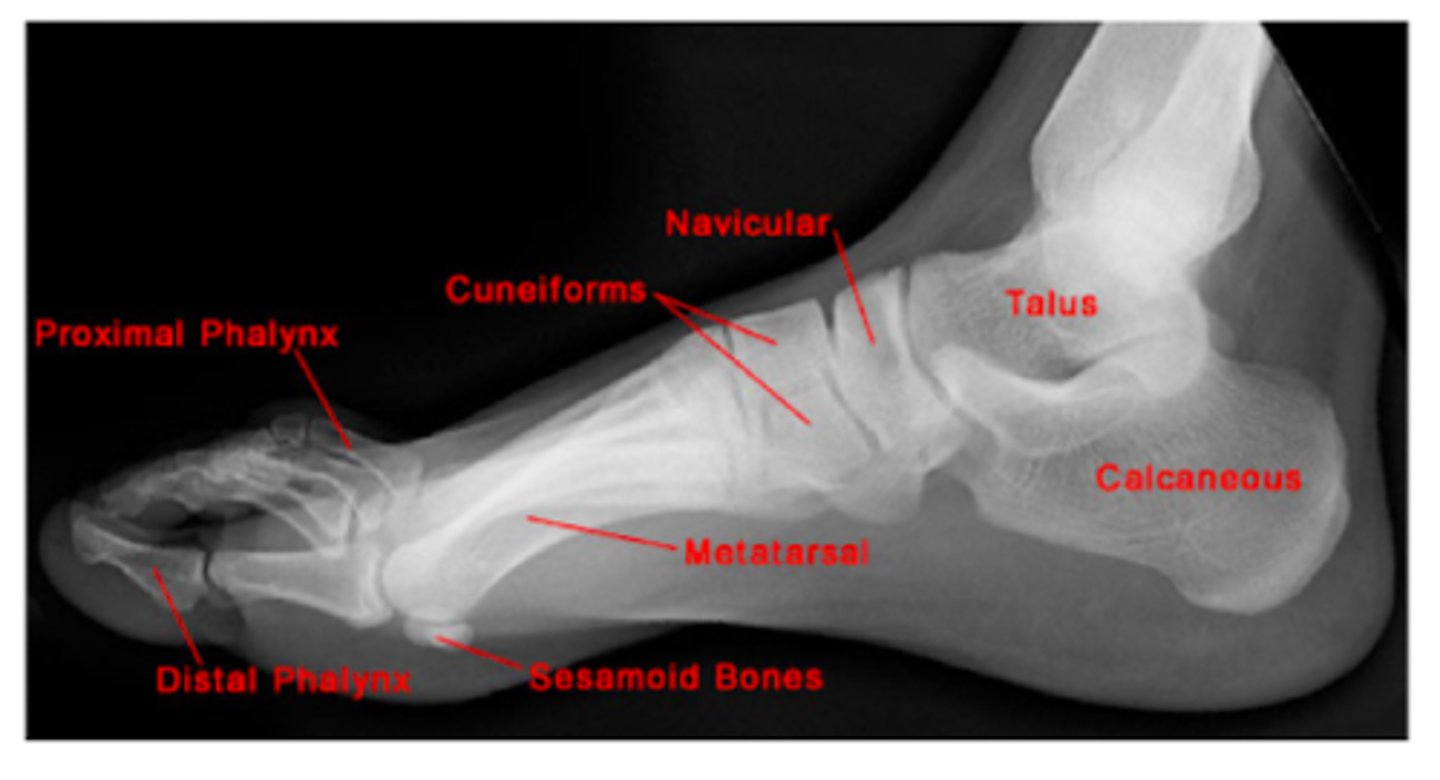

Review: Lateral Foot XR.

Review: Bones of the Foot.

What TWO bones comprise the FOREFOOT?

Phalanges

Metatarsals

What are the FIVE bones of the MID-FOOT?

Cuneiform x3

Navicular

Cuboid

What TWO bones comprise the HIND-FOOT?

Talus

Calcaneus (heel)